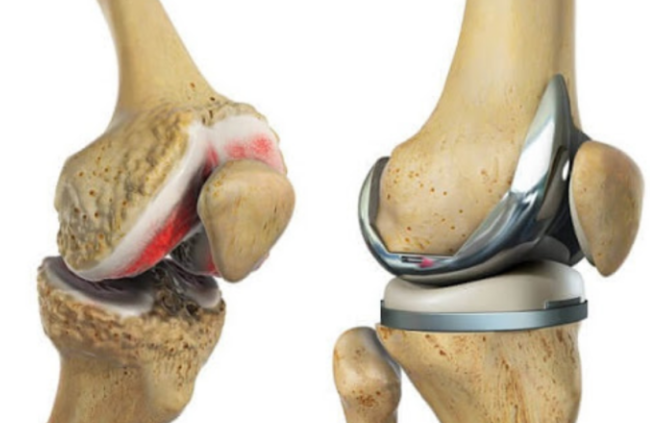

1. 무릎 인공관절 수술이란?

무릎 인공관절 수술은 퇴행성 관절염이나 관절 손상으로 인해 정상적인 생활이 어려운 분들을 위해 손상된 관절을 금속 또는 플라스틱 인공관절로 치환하는 수술입니다.

- 일반적으로 치환술이라고도 하며, 전치환(전체 교체)과 부분 치환술로 나뉩니다.

7. 무릎 인공관절 수명과 재수술 여부

- 평균 15~20년 수명 (일상생활 기준)

- 무리한 등산, 격한 운동은 피해야 수명 연장 가능